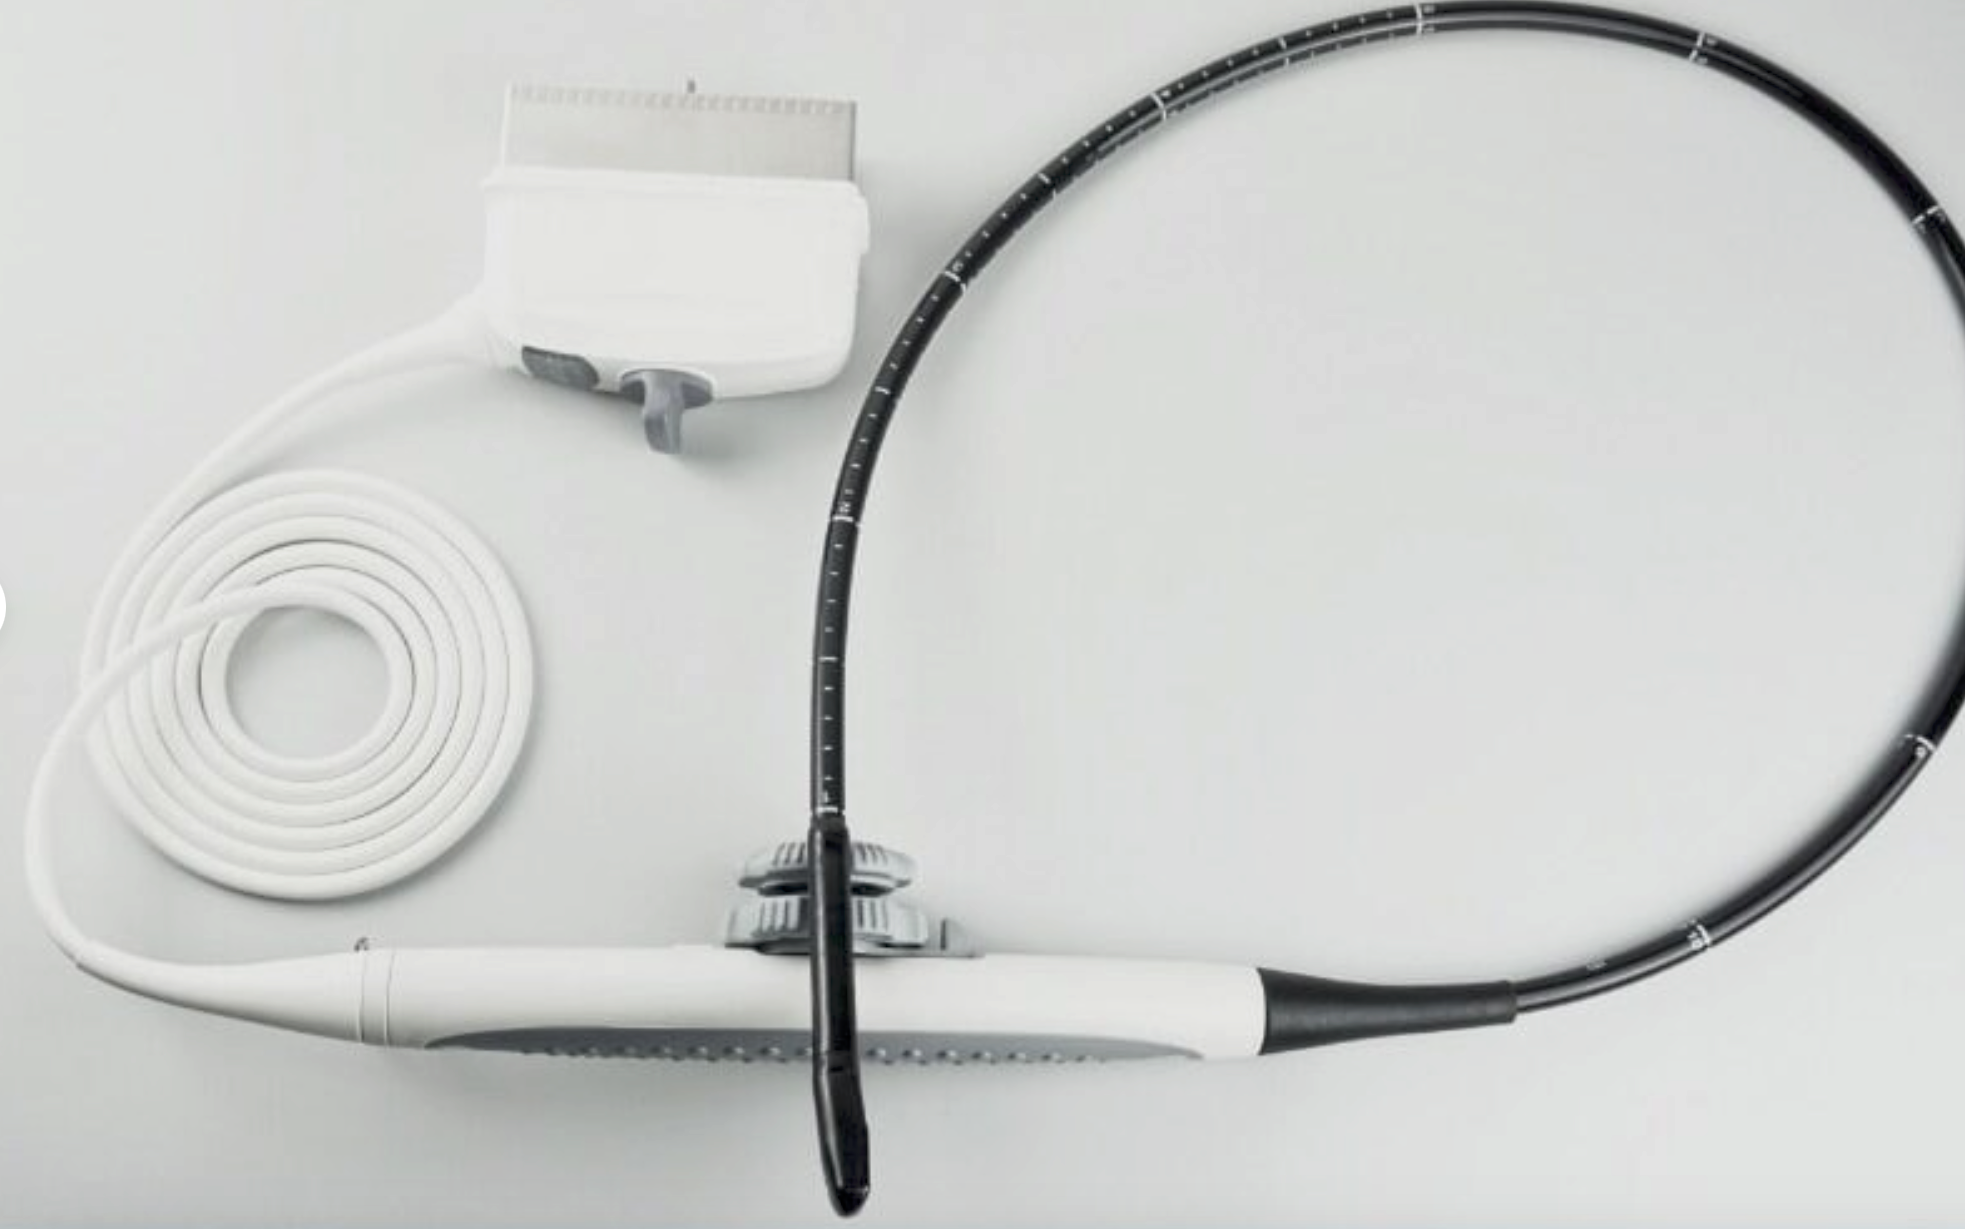

One of the key features of the Laptop Color Doppler Ultrasound is its portability. This means you can easily transport it between examination rooms or even take it off-site when necessary. Despite its compact size, it offers robust capabilities that rival larger, stationary units. Medical professionals appreciate the balance of convenience and high performance it offers.

Additionally, the device includes Power Doppler functionality, which enhances the ability to detect blood flow and other internal processes. This technology provides more detailed imaging, allowing for better patient assessment and treatment planning. The Doppler ultrasound functionality ensures that even the smallest anomalies can be detected with clarity and precision.